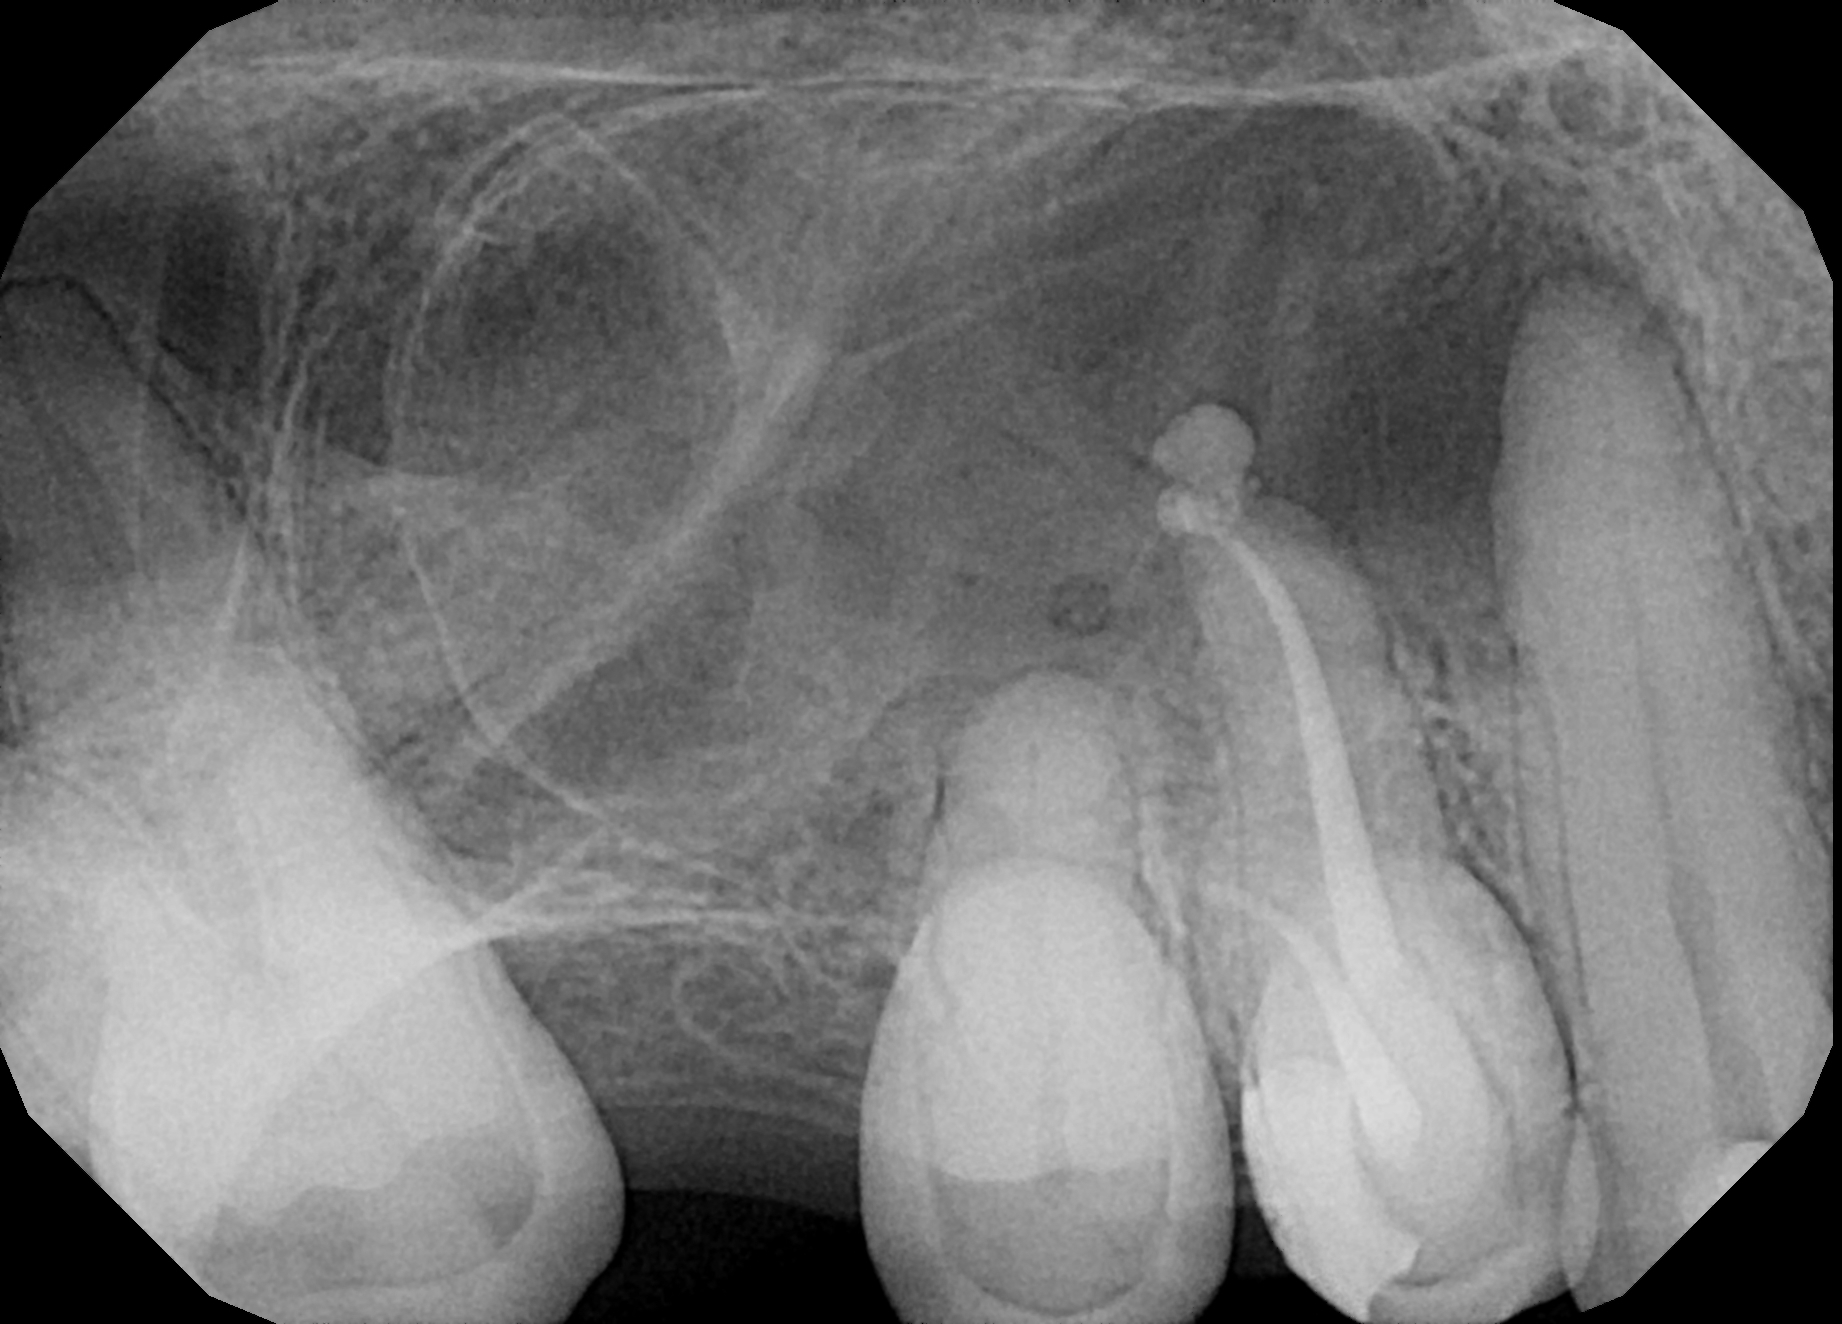

Fig.: 1

It is important to understand that when dentists work with rotary files, which typically rotates at approximately 300 rpm in the canal space, the flutes of the instrument are totally blocked just after the start of the motion. Therefore, most of the debris and cut dentine are packed into the lateral anatomy. This creates problems from the very beginning because of this blocking of already tight and narrow spaces, which are difficult to clean later. Improper instrumentation performed too fast with multiple strokes in one movement followed by lack of proper irrigation and activation leads to failures even when the radiograph shows beautiful white lines. We must not forget that anatomy is 3D (Fig. 1).